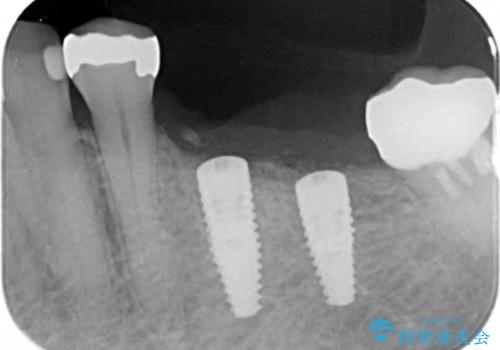

入れ歯ではなく、よりしっかりと噛めるようになるインプラント治療を希望されましたが、将来的な安定を見込むにはインプラント周囲の骨量が少ない状況でした。

舌側にある大きな骨隆起を除去するとともに、除去した骨と人工骨を用いてインプラント周囲の骨を造成します。

- 88万円(インプラント×2・アバットメント×2・クラウン×2・骨造成)費用は治療当時の料金となります

自家骨と人工骨による骨造成は、長期的に見て安定し吸収が少ないとされる骨の造成法です。

インプラント周囲に、必要十分な骨を作ることが長期渡りインプラントにトラブルを起こしにくい鍵となります。